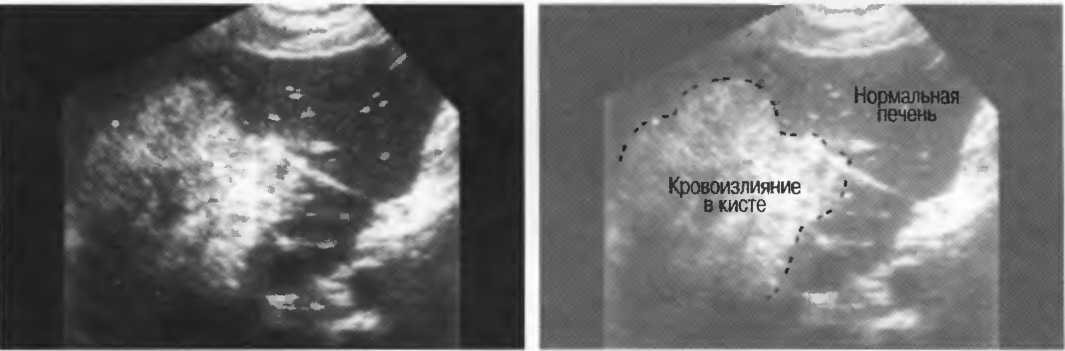

Кисты

Киста, как правило, визуализируется в виде анэхогенной зоны, при этом структуры, расположенные за кистой, обычно усилены: полость кисты анэхогенна, поскольку в ней нет структур с различным акустическим сопротивлением. В результате того что жидкость не поглощает ультразвук в такой же степени, что и ткань, эхо-сигналы от расположенных позади кисты структур гиперкомпенсированы сканером и выглядят усиленными — появляется эффект усиления задней стенки (рис. 14а,б).

Киста определяется в виде анэхогенной зоны с усилением по задней стенке. Если в кисте есть внутренние зхоструктуры, то они могут быть реальными или являться артефактами.

Артефакты могут определяться в любой кистозной структуре (такой, например, как мочевой пузырь или желчный пузырь) и чаще определяются ближе кпереди, становясь менее выраженными на глубине. Они исчезают или меняют свой характер при изменении положения датчика. Но истинные структуры в кисте, такие как перегородки, сохраняют свое местоположение независимо от положения датчика. Истинные отражения имеют место при наличии сгустка крови, гноя, некротической взвеси, и все это чаще визуализируется по задней стенке: если эти структуры не фиксированы к стенке, они изменяют свое положение при перемене положения тела пациента (рис. 16).